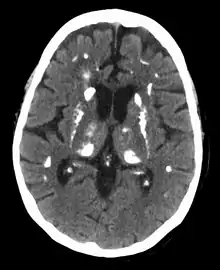

Calcification in the brain due to hyperparathyroidism